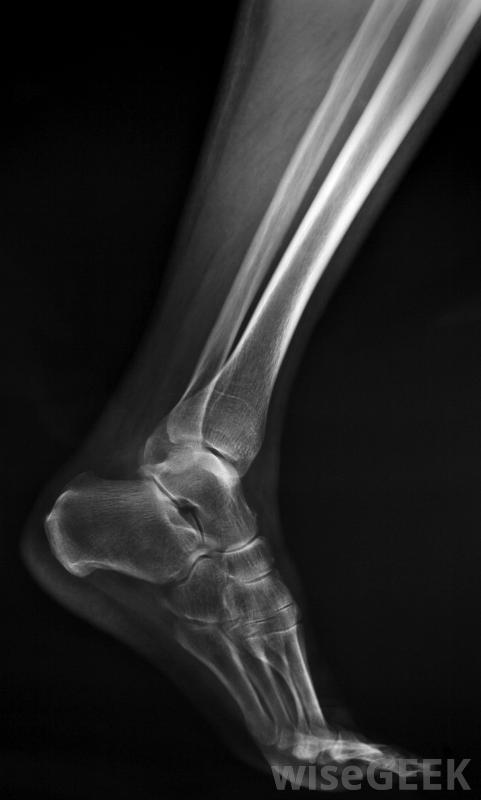

膝蓋示意圖,顯示腓骨。

腓骨是小腿較細的長骨。